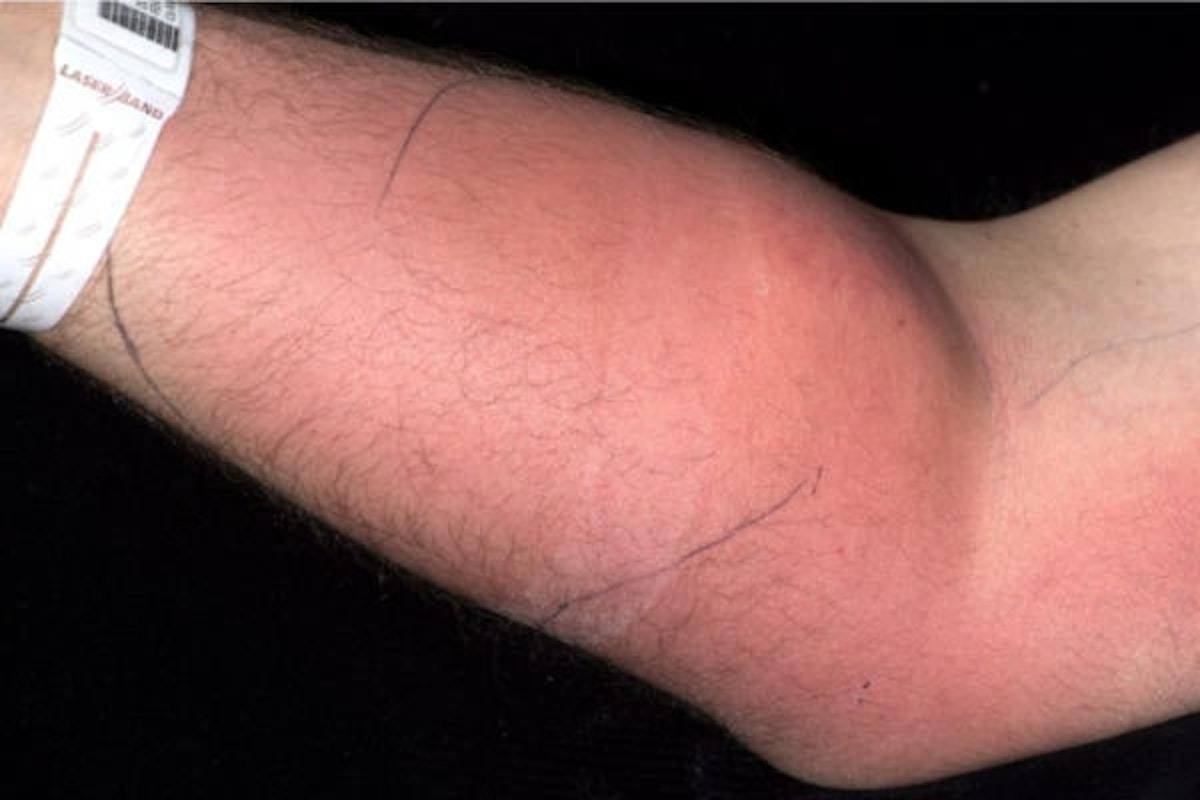

• 1 /4 Zwar hatte der 33-jährige Ire das Spital wegen anhaltender Rückenschmerzen aufgesucht, doch plötzlich drehte sich alles um seinen rechten Unterarm. Dieser war aus Sicht der Ärzte verdächtig rot angeschwollen.

(Bild: IMJ/L.Dunne et al.)

• 4 /4 Neben dem Abszess hatte sich der 33-Jährige mit seinem Tun eine schwere bakterielle Unterhautinfektion - eine sogenannte Zellulitis - zugezogen. Deshalb setzen ihm die Ärzte eine weitere Spritze, die dieses Mal antimikrobielle Wirkstoffe enthielt. Bevor die Behandlung jedoch abgeschlossen werden konnte, entließ sich der Patient auf eigene Faust.